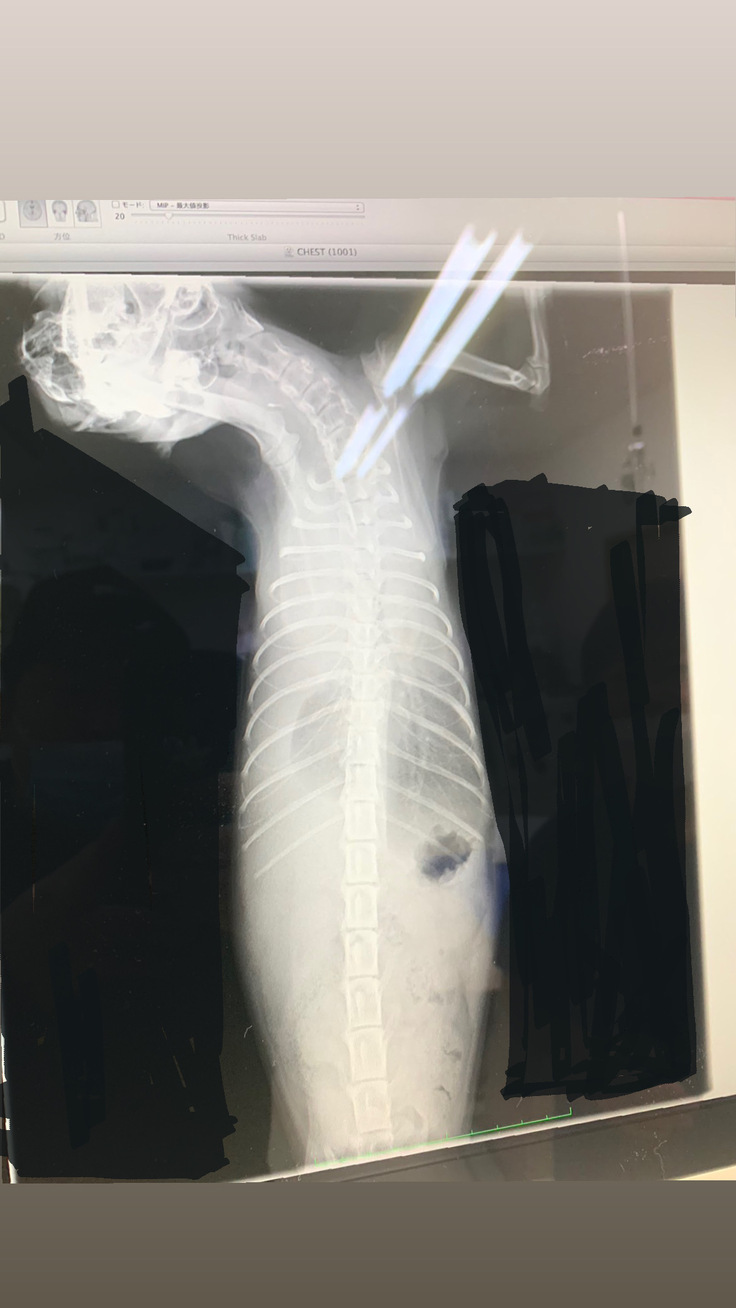

【レントゲン写真】

胸の白い部分が胸水だと言われて、真っ白な写真に驚きました。

胸水を注射で抜いてもらい、真っ黄色な胸水をみて驚きました。小さい体の中に300mlもの胸水が取れました。